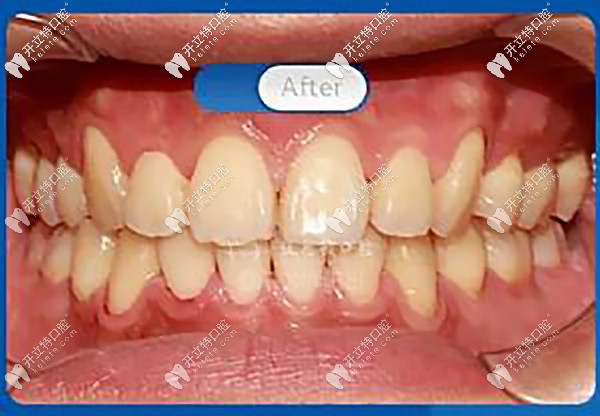

歷經(jīng)24個月終于完成了矯正,快看看我的變化吧!

正面看,內(nèi)收前牙,排齊牙列、牙中線,解除磨牙深覆蓋,恢復(fù)正常咬合關(guān)系。

笑容自信陽光有感染力

花了兩年的時間,摘下牙套之后真的有種整牙如換頭的感覺,嘴凸改善了,好看的下頜線也出來了,重要的是,大家都說我原來笑起來好看,現(xiàn)在的我再也不害怕微笑了。